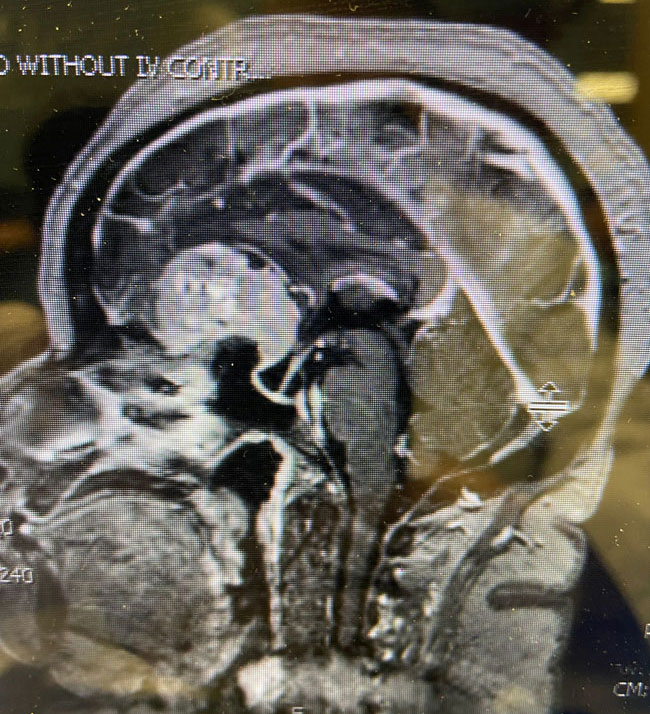

This is a 64 year-old woman with no significant past medical history who noted rapid deterioration of vision in her left eye 3 weeks earlier. She said it felt like there was a cloud over her eye. Ophthalmology evaluation confirmed poor vision in the left eye and ordered a brain MRI. The MRI demonstrated a large planum sphenoidale meningioma with significant compression on the optic nerves and optic chiasm and significant surrounding edema (Figures 1 a, b, and c). She was then referred to Dr. Michael Brisman for neurosurgical evaluation.